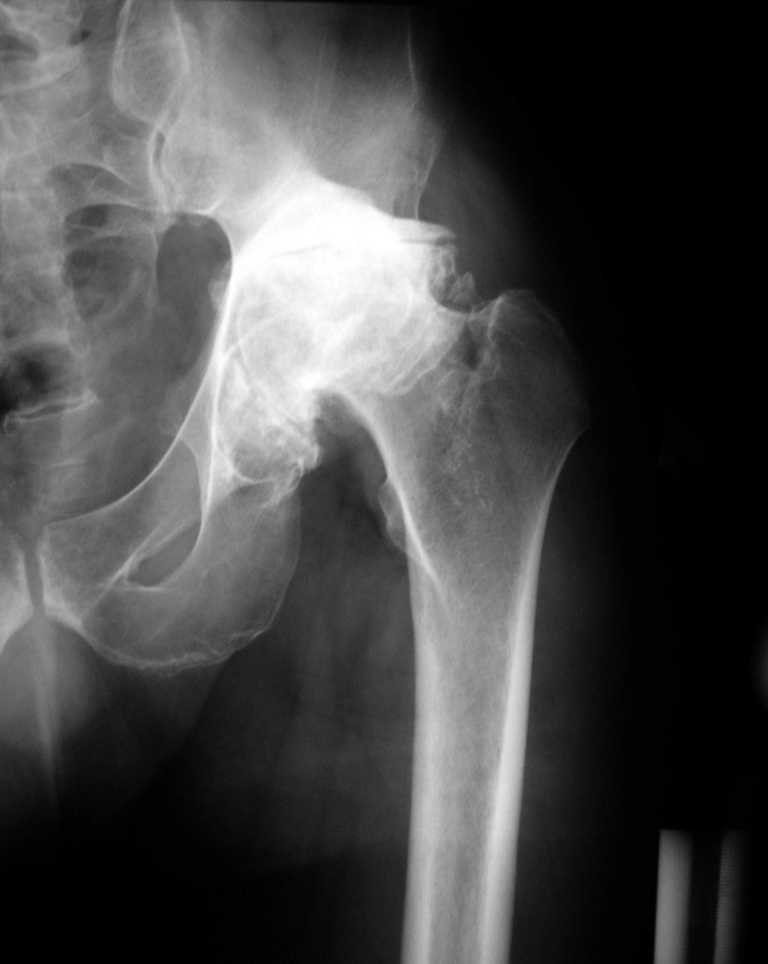

Еще одно наблюдение, неправильно сросшийся перелом заднего отдела ВВ с ввихом головки бедра 16-и летней давности.